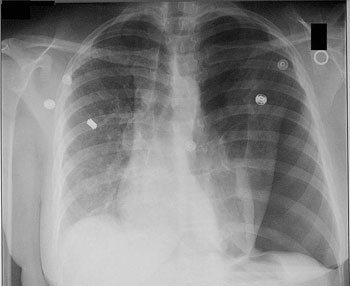

Les nombreux chapitres des deux tomes (treize chapitres pour le tome I et trente-neuf pour le tome II) sont émaillés de constatations et interprétations rendues possibles par le stéthoscope, tant pour les maladies cardiaques que pulmonaires, avec une prose plus discursive que pour la description de l’instrument. Laennec énumère les maladies pulmonaires détectables par son instrument ; le chapitre sur le pneumothorax est intéressant car, en l’absence de technique radiographique, l’auscultation médiate (avec stéthoscope), par la dissymétrie des sons entendus, permet sa mise en évidence sur l’être humain.

Figure 3 : Image par radiographie d’un pneumothorax (en bas à droite) (image WikiCommons, auteur Medical Cases)

Un pneumothorax est la formation d’une poche d’air en dehors du poumon, qui provoque l’affaissement de celui-ci. Il peut être spontané ou traumatique (suite à un choc). Un emphysème est une destruction des parois des alvéoles pulmonaires (qui peut être causée par le tabac – il était aussi causé, à l’époque, par la fumée des maisons chauffées au bois). Il provoque des difficultés respiratoires et peut provoquer un pneumothorax.